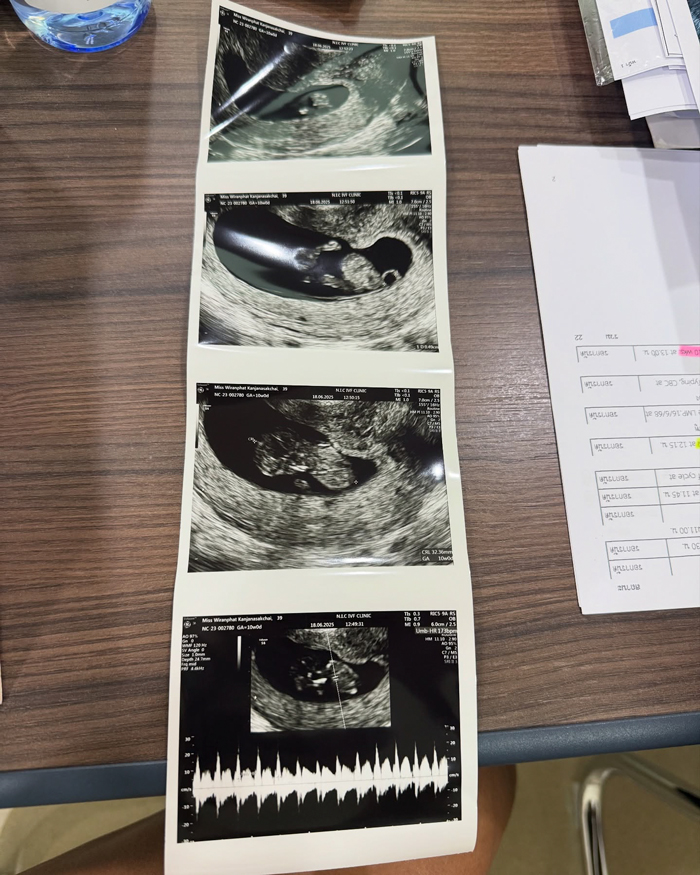

โดย ปาย สิตางค์ ได้ออกมาเผยภาพอัลตราซาวด์ลูกในท้อง พร้อมเปิดเผยว่า "ขอบคุณทุก ๆ กำลังใจที่ส่งมาให้ปายเสมอ เก็บไข่ 5 รอบ และกว่าจะท้อง สำหรับปาย มันไม่ได้ง่ายเลย และในที่สุด วันนี้ก็สำเร็จแล้วค่า ปายจะพยายามแบ่งปันความรู้และสิ่งดี ๆ ที่กว่าปายจะผ่านมาได้ อยากให้ทุกคนรอติดตามนะคะ"